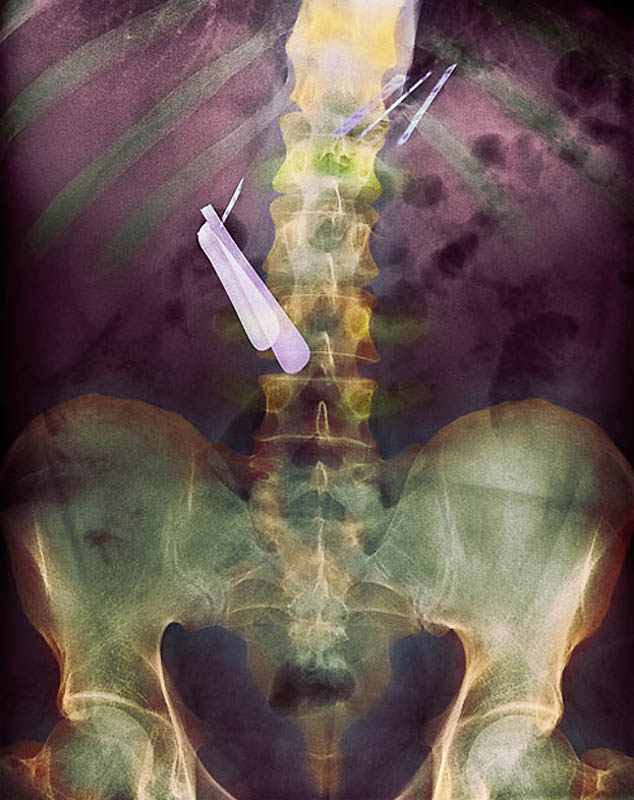

Цветной снимок предметов, которые проглотил пациент, и которые застряли в его кишечнике, включая ложку и лезвие

Цветной рентген желудка пациента, который проглотил бритву (по центру слева) и лезвия (вверху справа)